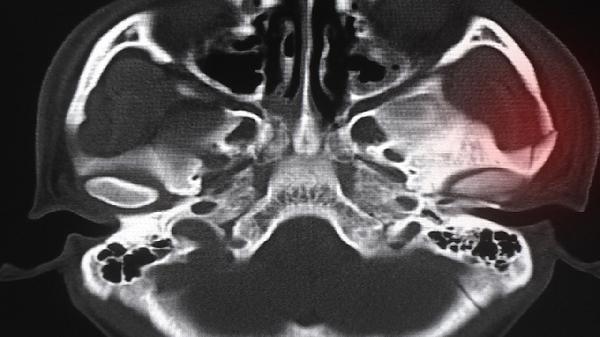

对于湿热型腰椎间盘突出伴随下肢放射痛,四妙丸可能辅助减轻神经根水肿。但需在CT或MRI确诊后,与牵引、营养神经药物协同治疗。严重椎管狭窄或马尾综合征患者不宜单独使用。